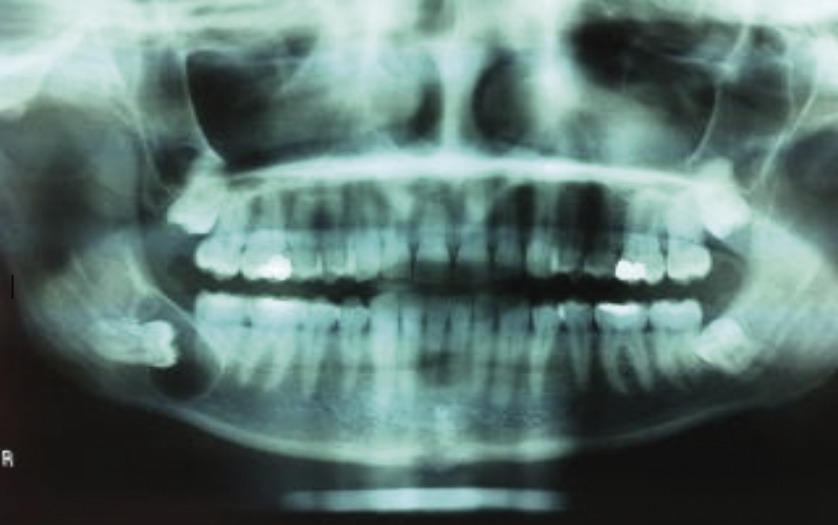

Un scanner est réalisé : il objective un kyste de 2 cm de grand axe, occupant la partie postérieure de la branche horizontale mandibulaire, repoussant la dent n° 48 vers l’extrémité de l’angle mandibulaire et se développant au contact du nerf dentaire inférieur (fig. 2 ).